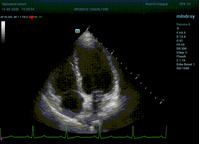

С появлением В режима реализовалась возможность визуализации всех сегментов миокарда из парастернальных и апикальных сечений. Метод Teicholtz в широкой практике сменился методом дисков. Метод дисков, или метод Simpson, позволяет разбить левый желудочек на 20 дисков, с расчетом объема каждого из них. Используя 2 перпендикулярных сечения, апикальные двух и четырех камерное, мы приближаемся к значению реального объема левого желудочка. Исследователь обводит интерфейс эндокард – кровь в фазу диастолы и фазу систолы. Линия простирается от кольца митрального клапана и до кольца митрального клапана, четко разграничивая объем желудочка от предсердия. Для достоверного изменения необходимо использовать ЭКГ канал.

Обводить вручную эти линии занимало много времени, однако результат того стоил. Следующим шагом стало появление Spline технологии, позволяющее расставлять точки и автоматически их соединять. Такой способ планиметрии контура эндокарда значительно сократил время измерения.

Что могут предложить современные приборы? Приборы нашего времени являются мощными вычислительными машинами, способными обрабатывать полученную информацию даже без помощи человека. Система автоматического вычисления фракции выброса – AUTO EF на приборах серии Resona компании Mindray сделает все за вас. За пару секунд прибор сам отыщет нужную фазу сердечного цикла и произведёт измерение и расчеты, а также покажет график изменения объема в сердечном цикле. От Вас требуется только получить качественное 4С и 2С сечение. Впрочем, прибор всегда оставляет возможность коррекции, если доктор имеет свое мнение на расположение точек планиметрии или момента измерения по ЭКГ каналу.